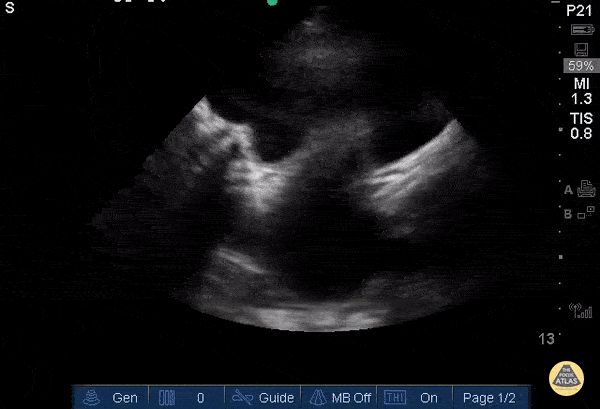

13yoF with worsening abdominal pain and back pain x3 months, found to have large bilobed pelvic mass consistent with hematocolpos/hematometra due to imperforate hymen. Transabdominal ultrasound using a 5-1MHz phased array probe in the transverse plane 2cm above pubic symphysis. A large hypoechoic structure within the uterus is seen displacing the bladder superoanteriorly with posterior acoustic enhancement. US can demonstrate retained old blood as a hypoechoic cystic structure and monitor resolution after hymenectomy. (Hassani 1978)